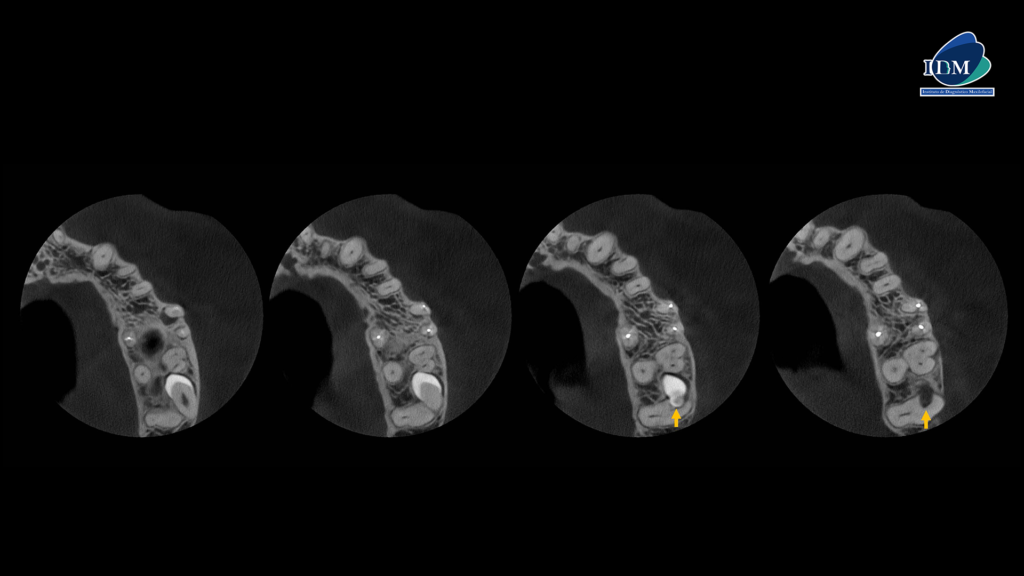

En el estudio ampliado mediante tomografía computarizada de haz cónico (TCHC), se observa una pieza dentaria supernumeraria localizada en posición vestibular respecto a la raíz de la pieza 28. La corona de esta pieza supernumeraria está en contacto con la raíz distovestibular de la pieza 27, según se aprecia en los cortes axiales. Asimismo, se identifica una anomalía de desarrollo en dicha pieza supernumeraria, compatible con perla del esmalte en su región cervical, la cual está asociada con reabsorción radicular externa de la pieza 28, observada en los cortes tangenciales y transaxiales.

CORTES AXIALES